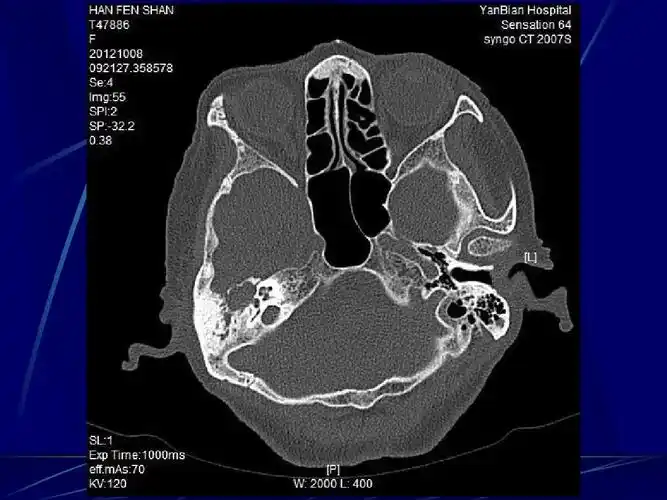

三叉神经痛,面肌痉挛手术前的主要影像学检查

面神经解剖及常见病变影像诊断

面神经解剖及相关病变